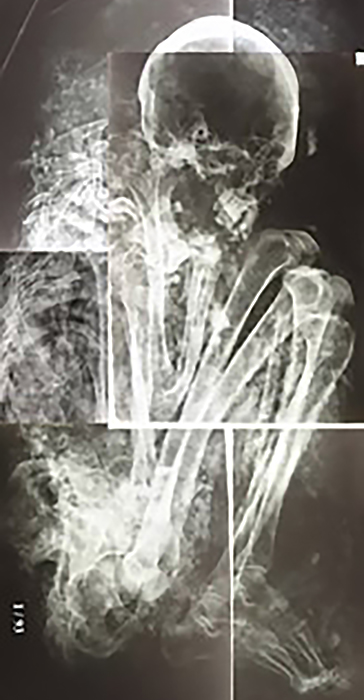

Esta gran reunión académica se celebra cada tres años y congrega a investigadores de todo el mundo. Abarca distintas especialidades y perspectivas: desde la arqueología e historia hasta la biología, la bioarqueología y la antropología forense. Se aborda también el delicado tema de los aspectos éticos de la exhibición pública y la divulgación de restos humanos momificados.

La próxima edición del congreso, a realizarse en Cusco, toma como base las ideas del ámbito andino sobre la muerte y el universo de los ancestros (mallqui), que guarda una conexión permanente con el mundo de los vivos. En la materialidad de sus cuerpos, los difuntos llevan testimonio de su época que, gracias a la ciencia, llega al presente como lección de vida.

Los mallqui nos brindan evidencias de su diversidad étnica y genética, su dieta, su farmacopea, sus creencias y rituales. A través de ellos podemos conocer el grado de salud y satisfacción de necesidades básicas para cada población y tiempo. Los científicos ayudan a rescatar el mensaje de los ancestros para contribuir a la construcción de un mundo mejor, desde el nivel de individuos hasta el de ecosistemas, porque conociendo los antecedentes, orígenes, causas, procesos y condicionantes de las enfermedades, las respuestas y conductas humanas y los efectos de todas esas interacciones en la salud de nuestros antepasados, podemos traer importantes lecciones al presente. Por ejemplo, el análisis de momias andinas contribuyó en el descubrimiento del papel que tuvieron los mamíferos marinos en la propagación de la tuberculosis a nivel mundial.